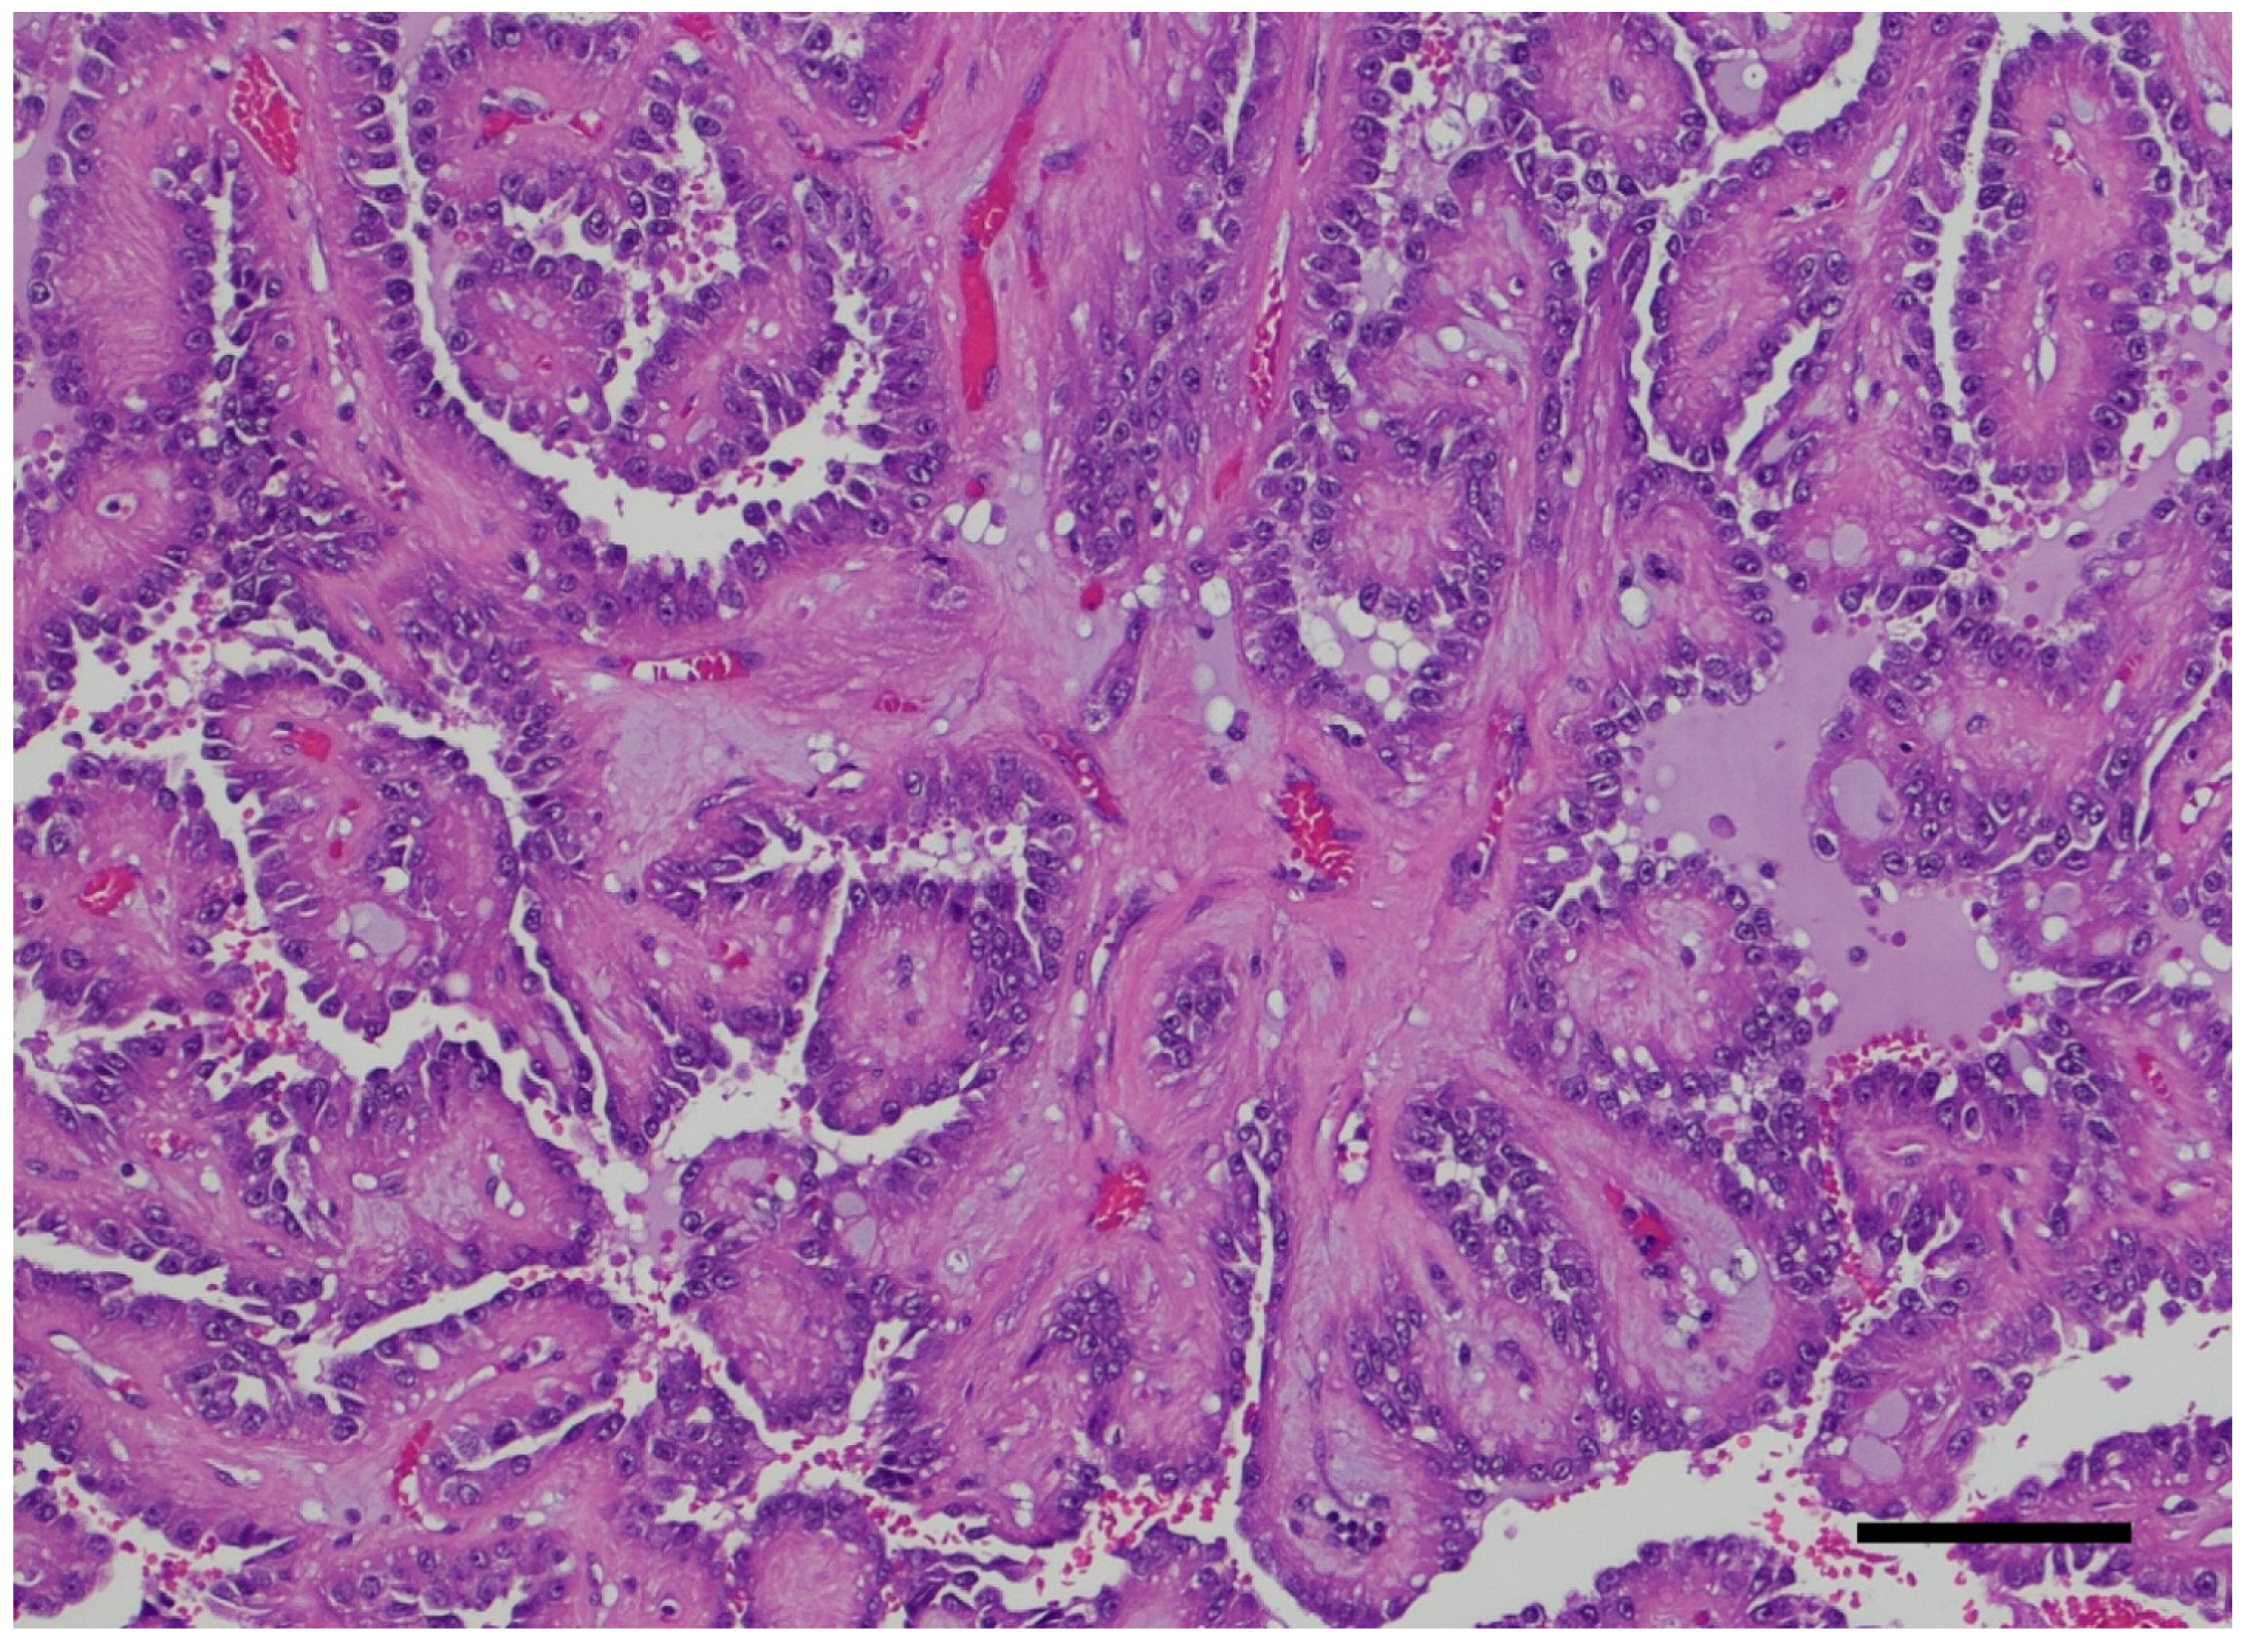

- Na, K.Y.; Kim, H.S.; Park, Y.K.; Chang, S.G.; Kim, Y.W. Multifocal renal cell carcinoma of different histological subtypes in autosomal dominant polycystic kidney disease. Korean J. Pathol. 2012, 46, 382–386. [Google Scholar] [CrossRef] [PubMed]